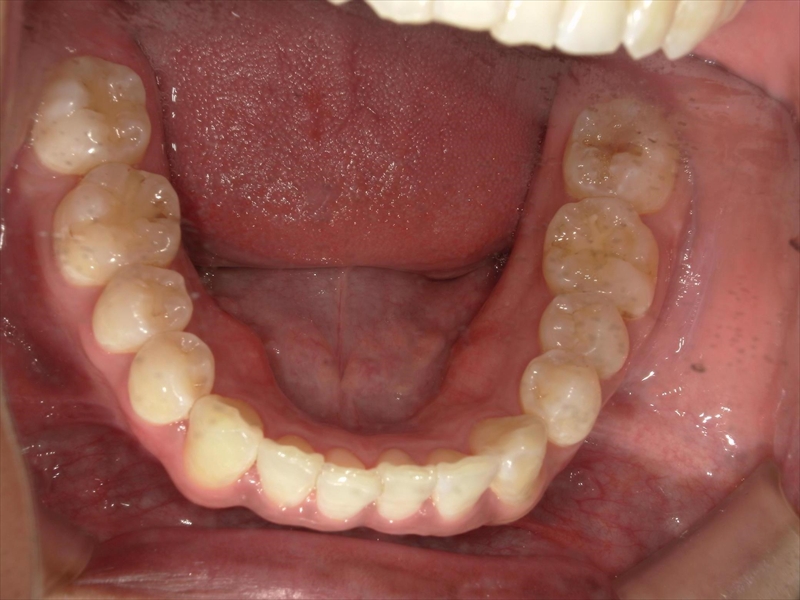

- 下あごの前歯もがたついている(叢生)

上あご同様、スペース確保のため、両側1~5番目までを各0.5ミリ(計5.5ミリ)削ることと、奥歯から順に奥へ下げながら外側へ広げる計画を立案しました。